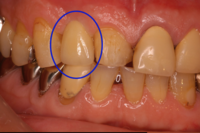

インプラント治療前

◆治療内容

前歯にインプラントを1本埋入し、アバットメントを装着。

最終的な補綴物を装着しました。